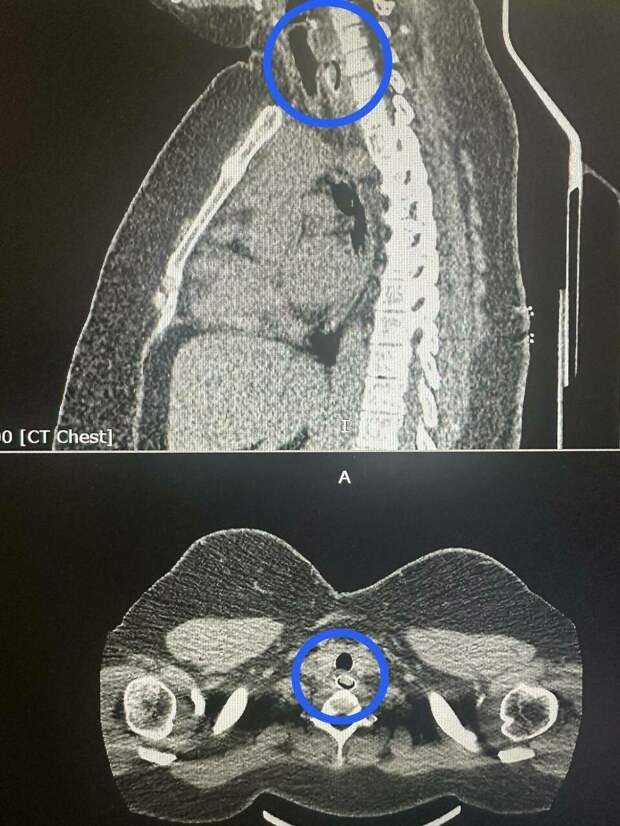

Андагы табиблар санавиация линиясе буенча РКБ торакаль хирурглары белән элемтәгә чыга. КТ ясагач, өрек төшен авыздан гына чыгарып булмавы ачыклана. Шуңа күрә пациентны Республика клиник хастаханәсенә китерәләр.Хирурглар катлаулы операция ясый: алар муенны һәм үңәчне кисеп, өрек төшен ала.